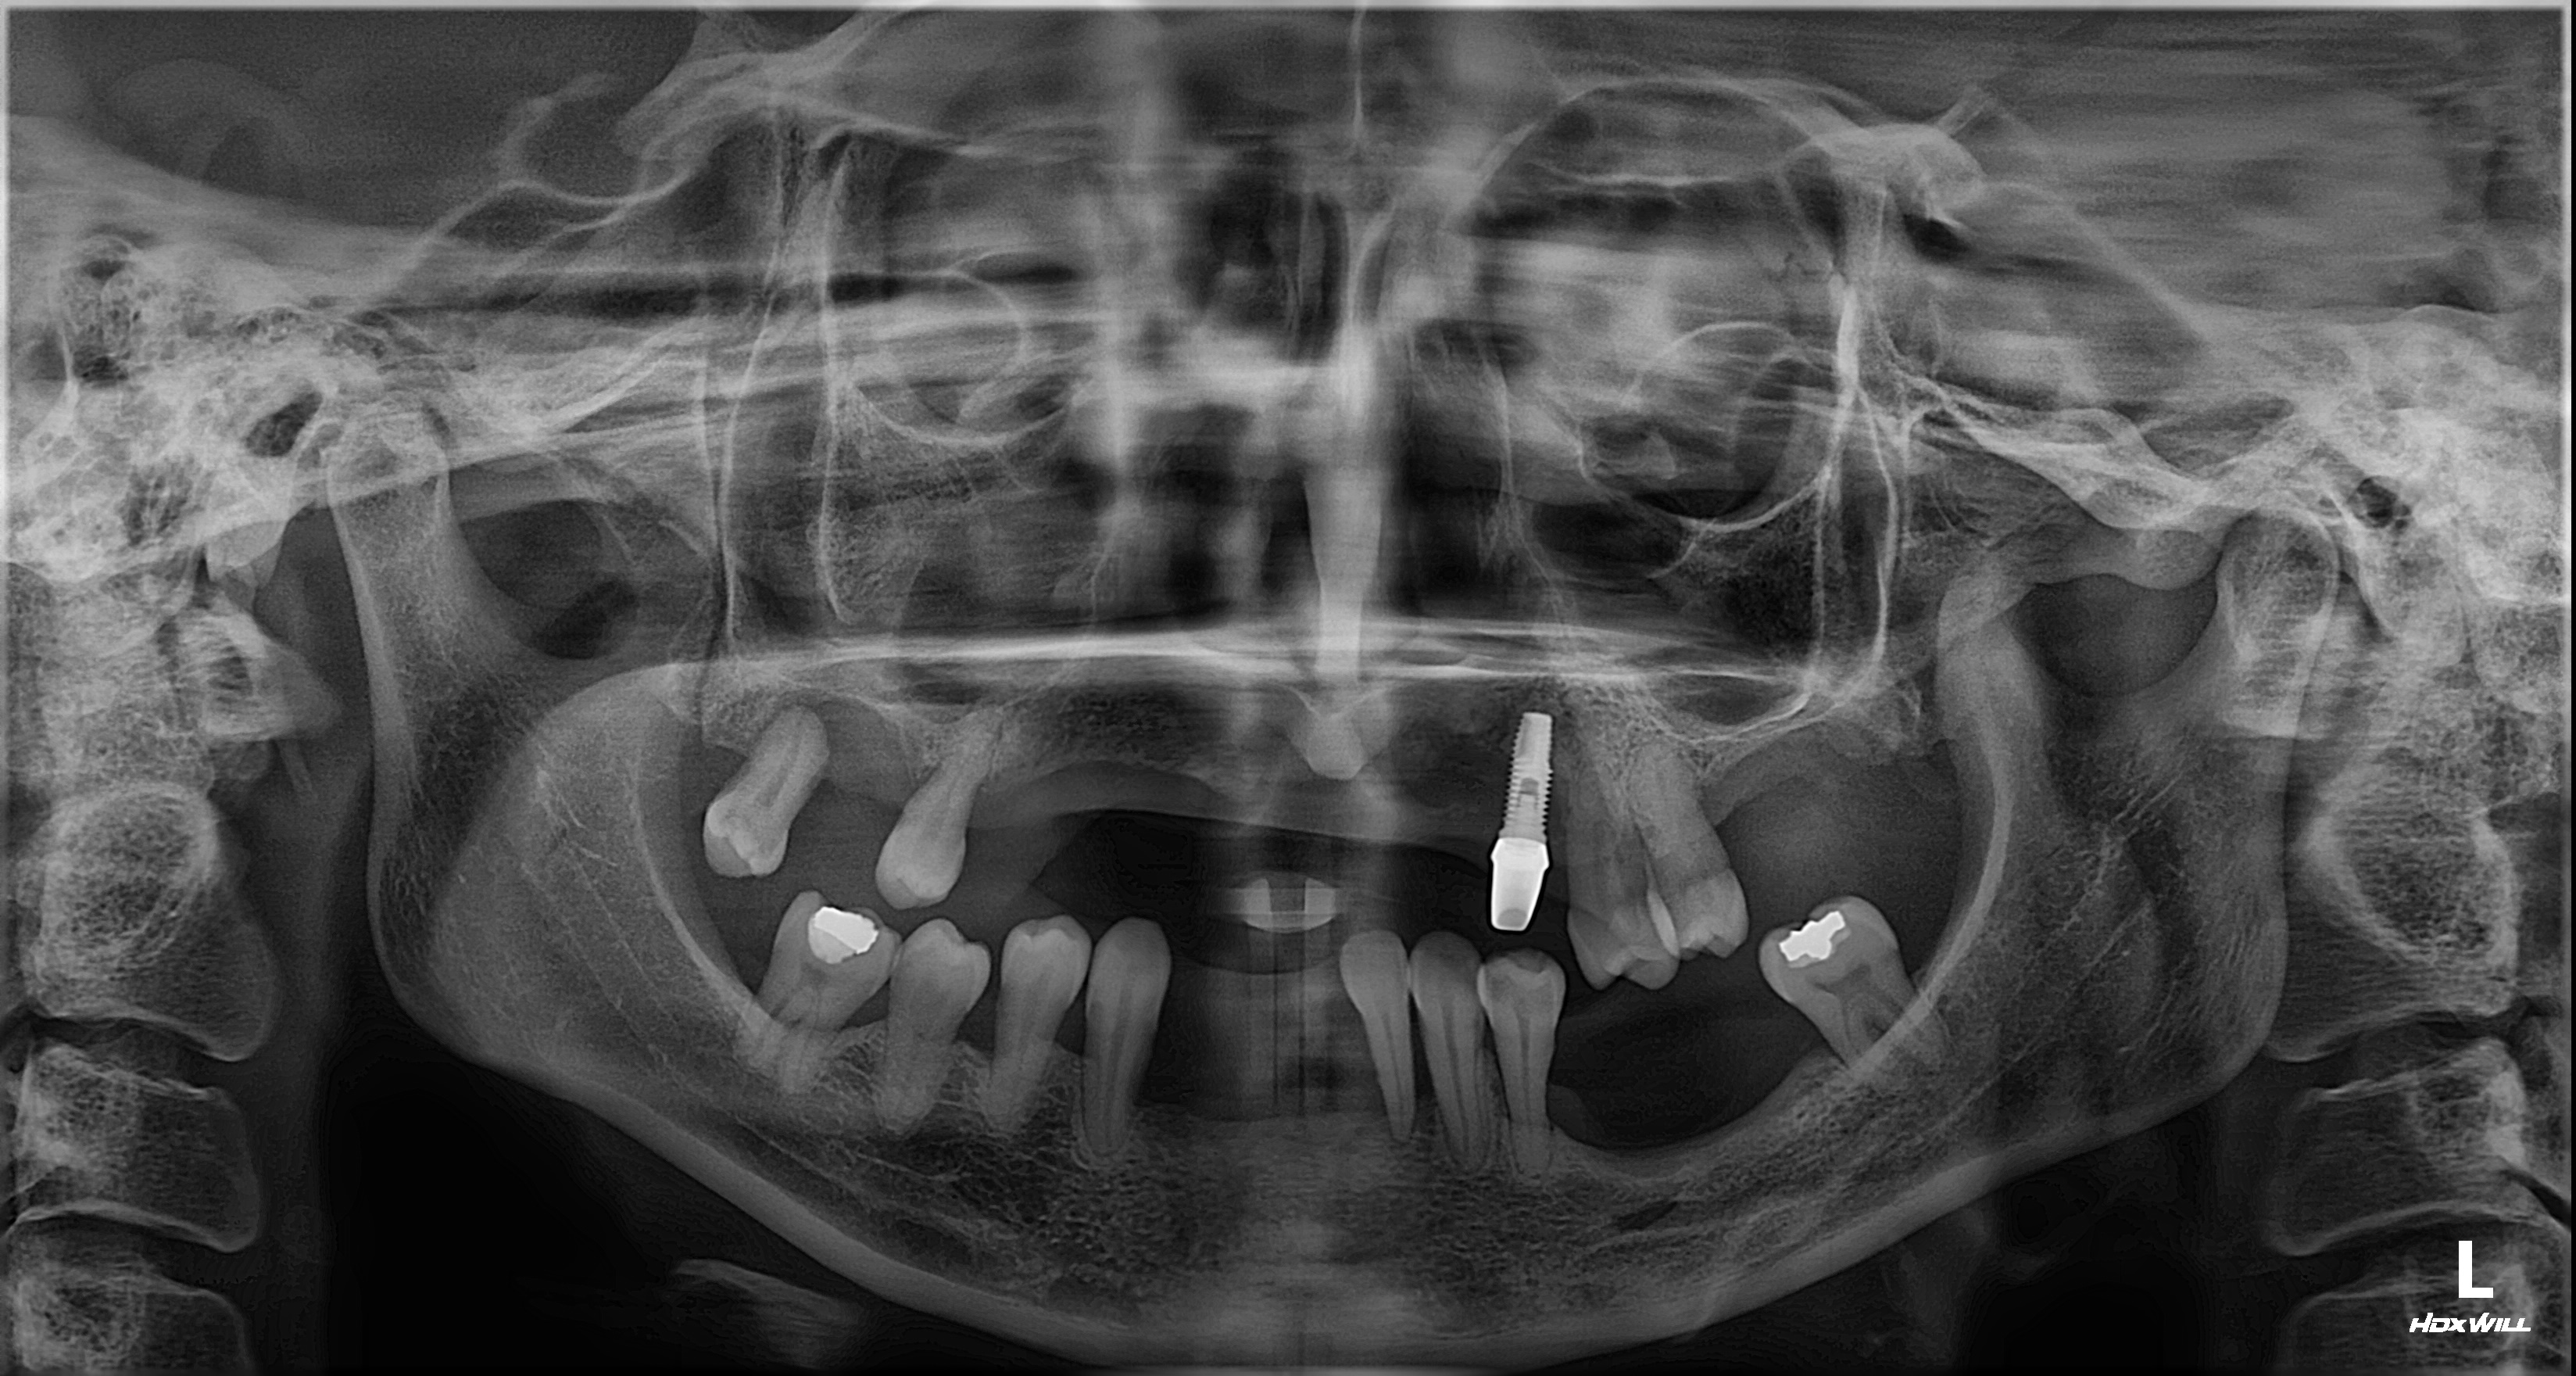

촬영일시: 2024.05.02